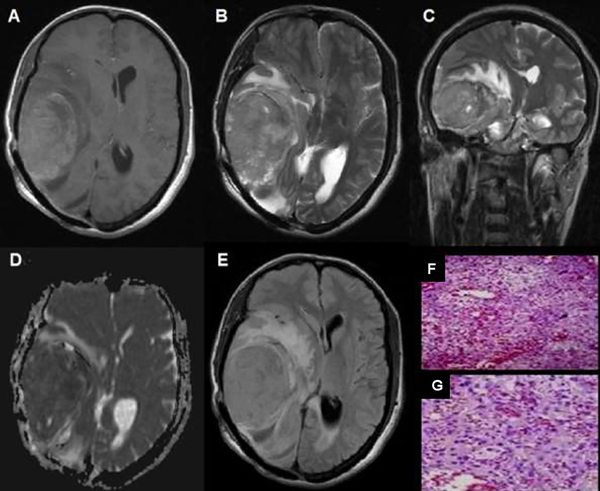

Figura 3. Meningioma rabdoide, grado III OMS. (A) RM axial T1: Meningioma temporoocipital derecho con edema perilesional significativo (flecha). (B) RM axial T2: Comportamiento heterogéneo con edema perilesional (flecha).(C) RM coronal T2: comportamiento hiperintenso con abundante edema perilesional. (D) Mapa de ADC:Comportamiento hiperintenso con disminución de intensidad (flecha). (E) RM FLAIR axial: Lesión extensa con abundante edema perilesional, (F y G) Microscopía: Meningioma con amplios sectores de diferenciación rabdoide, presencia de pleomorfismo y atipia nuclear, que alterna con sectores fusocelulares, necrosis y más de 20 mitosis por 10 campos de aumento.